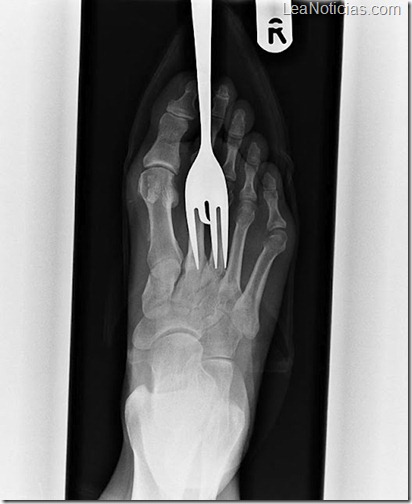

Radiografía de un paciente que acudió al hospital con un tenedor clavado en su pie.

Otro paciente con un tenedor clavado en su pie.